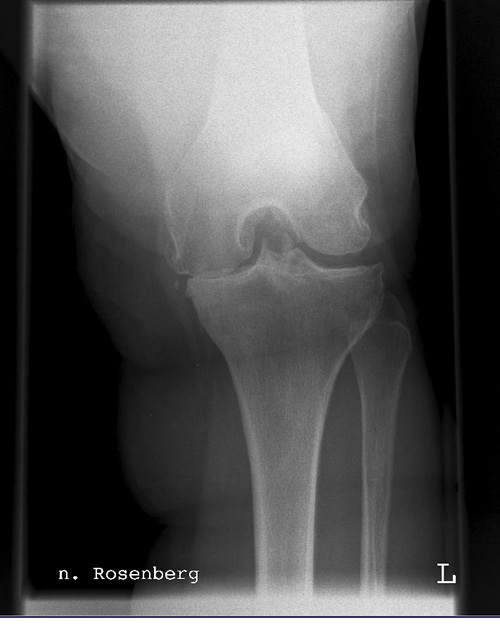

Rosenbergaufnahme

Kassette/Abstand

Format 18/24 / FFA 1,05m

Lagerung

Patient steht mit dem Gesicht zur Röntgenplatte und kann sich dort mit den Händen für ein besseres Gleichgewicht abstützen. Die Aufnahme erfolgt beidbeinig bei 45° Kniebeugung im dorsoventralen Strahlengang.

Zentralstrahl

Die Röhre wird ca. 10° nach caudal geneigt und zielt auf Mitte Kniegelenk.

Qualitätskriterien

Freier Einblick in die Fossa intercondylaris, Tibiaplateau muss strichförmig dargestellt werden.